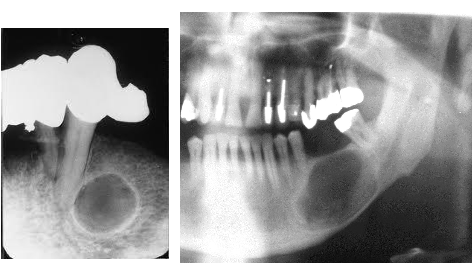

What is an Odontogenic myxoma?

Origin: Odontogenic connective tissue fibroblasts of the developing tooth germ.

Age: Young adults 2nd-4th decades

Frequency: Rare

Site: Posterior maxilla or mandible

Size: Variable

Shape: Multilocular – honeycomb or soap bubble

Outline: Well defined with variable cortication

Radiodensity: Radiolucent with fine radiopaque internal septa often arranged at right angles to each other

Effects: Displaced teeth occasionally resorbed, may be associated with an un erupted tooth cortical expansion / breach.

What’s an aneurysmal bone cyst?

Age: Adolescents and young adults under 30

Site: Commonly body / posterior mandible

Size: Can become very large

Shape: Unilocular / Multilocular – may be soap bubble appearance

Outline: Smooth and well defined

Radiodensity: Radiolucent with faint random trabeculation

Effects: Teeth displaced uncommonly resorbed Ballooning expansion Rare cortical perforation